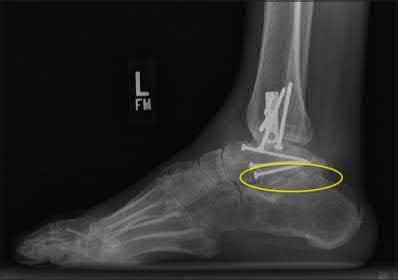

A 25-year-old male sustains an ankle fracture dislocation and undergoes open reduction and internal fixation. He returns to clinic five months following surgery complaining of continued ankle pain and instability with weight bearing. His immediate post-operative AP radiograph is seen in Figure A. Which of the following could have prevented this patient from developing persistent pain?

The patient presents with continued ankle pain and instability following open reduction and internal fixation. The radiograph in figure A demonstrates inadequate restoration of fibular length, likely leading to continued tibiotalar instability.